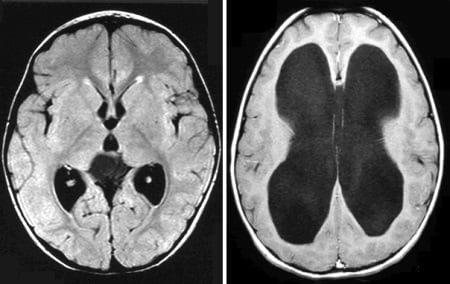

- По данным МРТ (магнитно-резонансной томографии) и КТ (компьютерной томографии).

- Судят по степени разрежения краев желудочков мозга и расширению жидкостных полостей.

На практике в большинстве случаев для более точной постановки диагноза и степени развития заболевания используется дифференциация симптомов клинического проявления гипертензии в сочетании с результатами аппаратного исследования головного мозга.